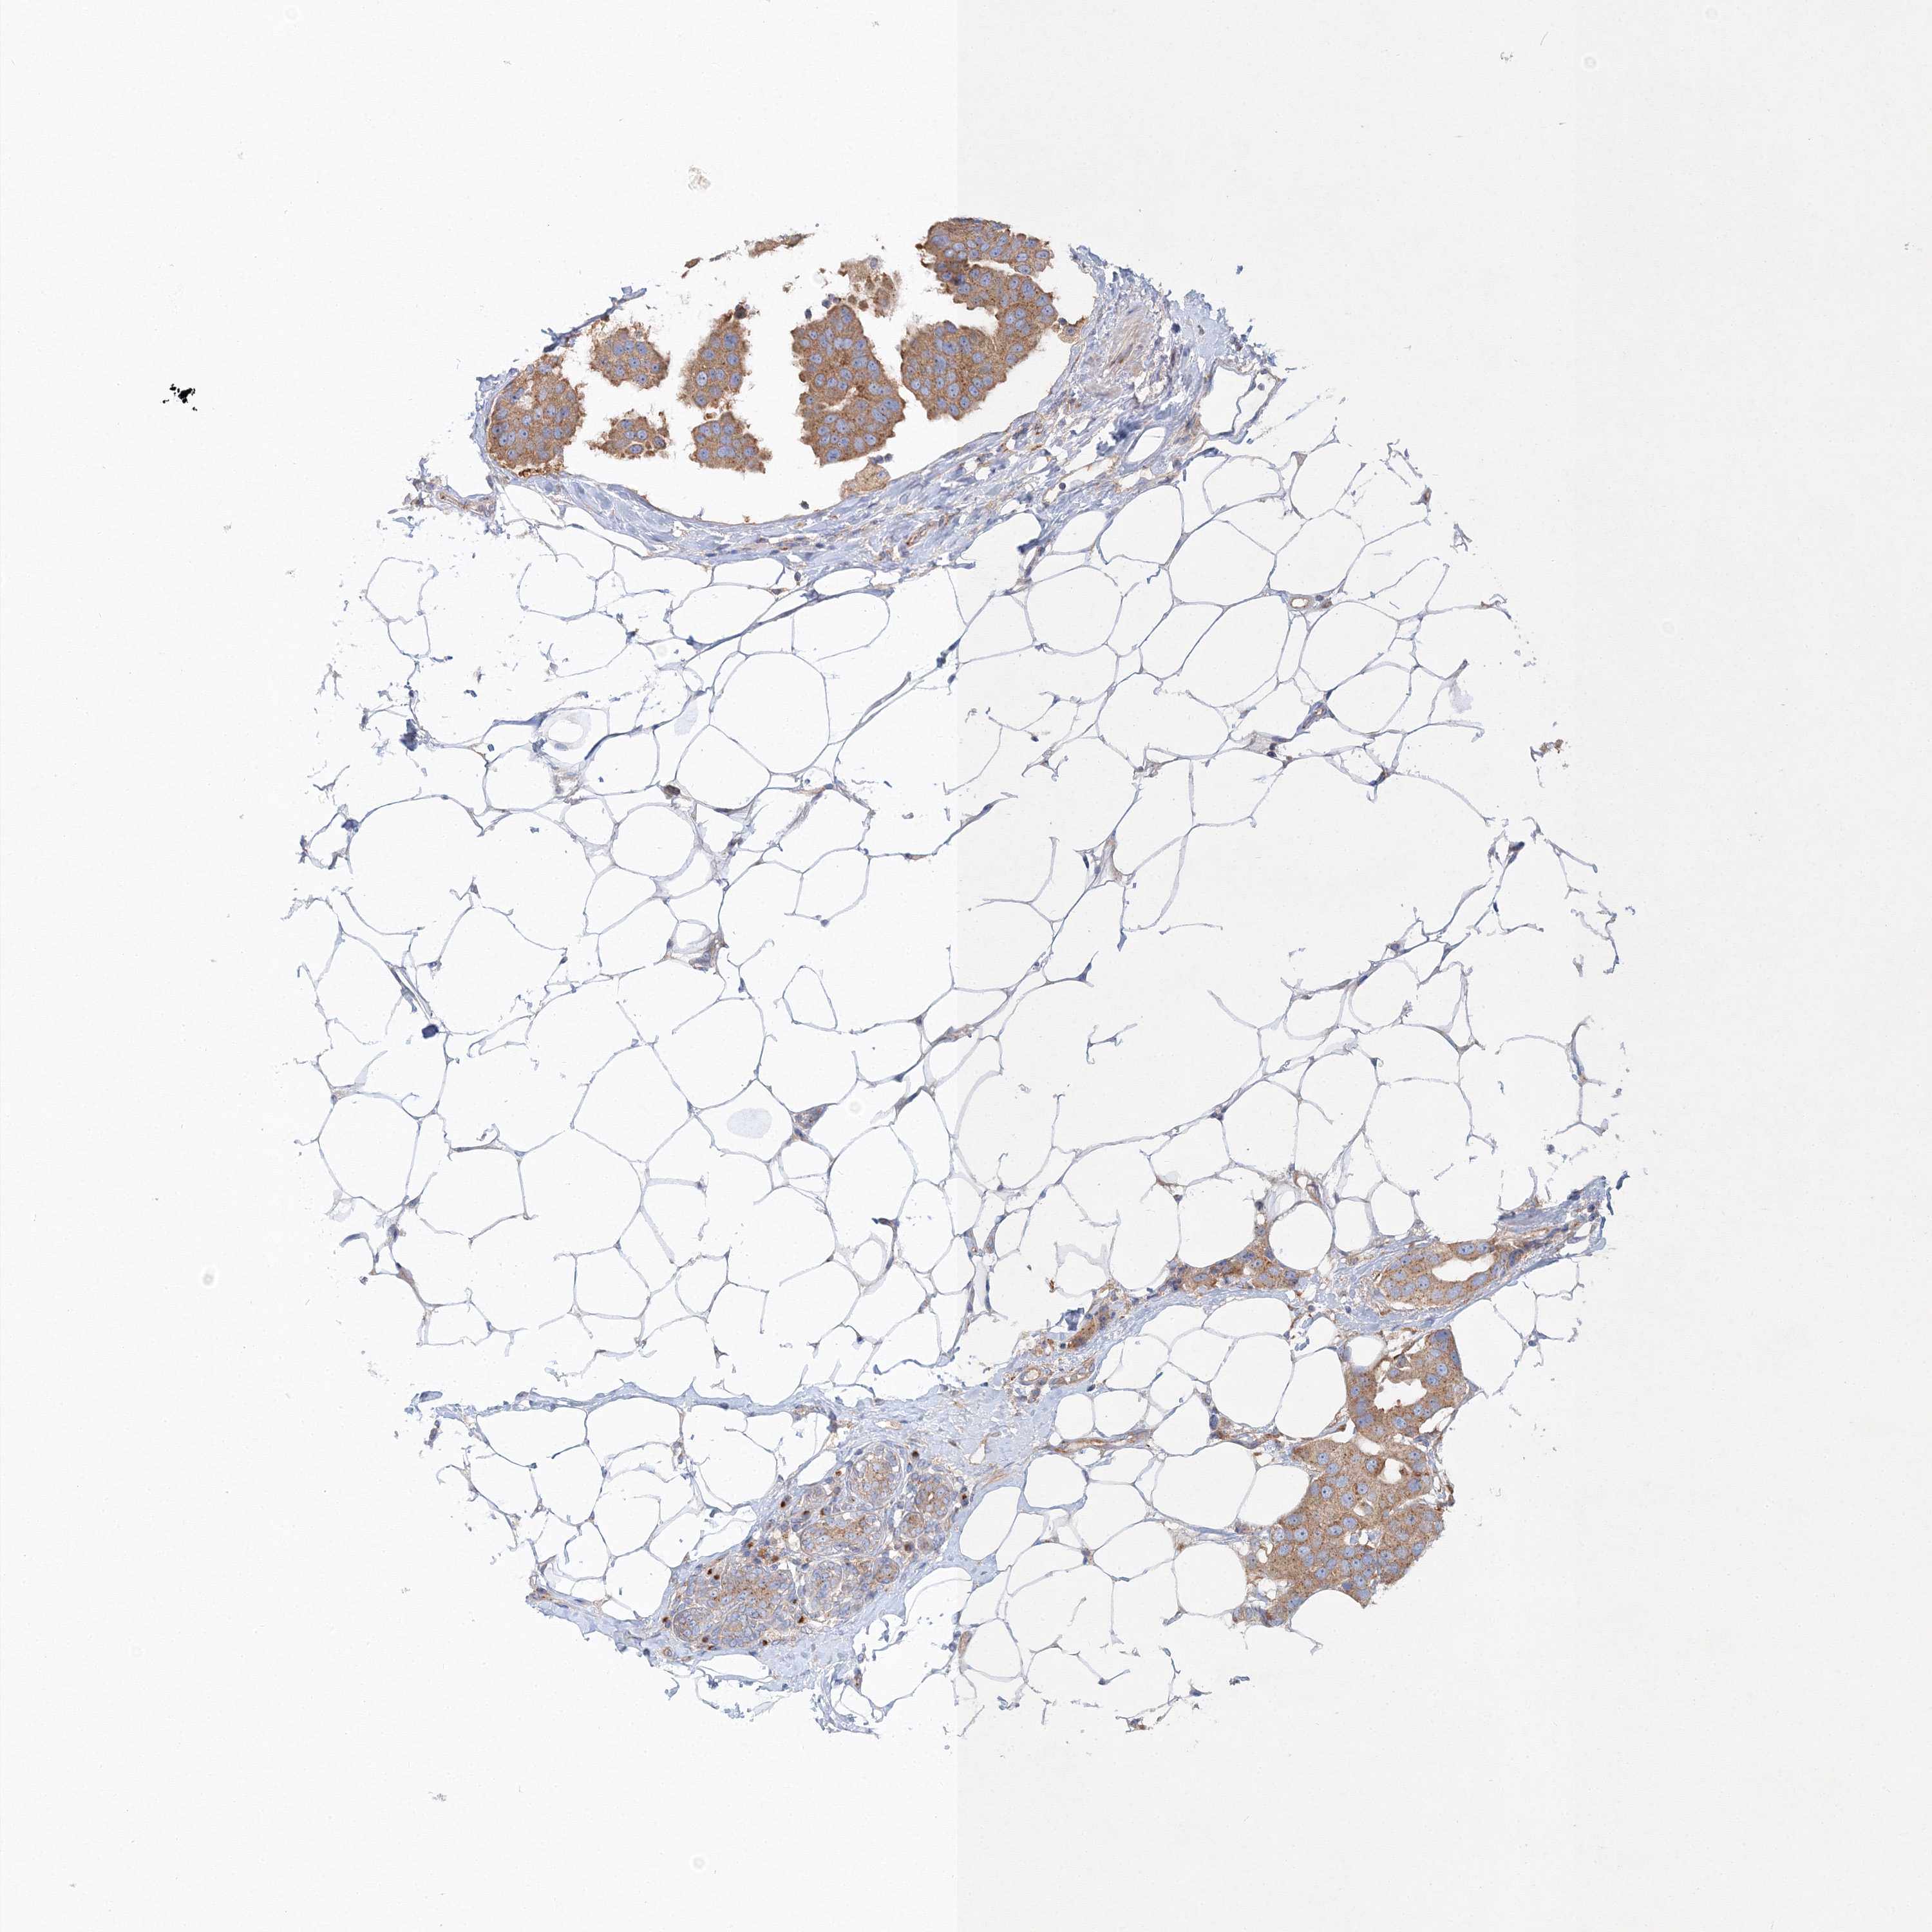

CANCER BREAST CANCER Show tissue menu

BRCA TCGA BRCA VALIDATION PROTEIN EXPRESSION